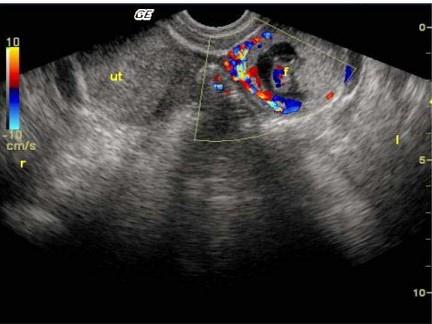

问题 女性,25岁,停经47天,阴道不规则出血1周。尿妊娠试验阳性。结合超声图像,最可能的诊断为?(?)

选项 A.附件炎性包块 B.宫外孕 C.卵巢癌 D.子宫肌瘤 E.畸胎瘤

答案 B